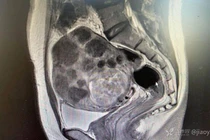

(Kiến Thức) - Phát hiện u xơ tử cung cách đây 5 năm, bệnh nhân 42 tuổi không hề điều trị. Chủ quan suốt thời gian dài đến khi bụng to bất thường, người phụ nữ đi khám rồi ngỡ ngàng phát hiện tử cung “mọc” u chi chít như sung.

Trang Sohu đưa tin, bệnh nhân 42 tuổi có tử cung “mọc” u chi chít như sung sống tại Trung Quốc. Người phụ nữ nhập viện trong tình trạng bụng phình to, không đau, không ra máu âm đạo hay tiết dịch bất thường. Ngoại trừ sự thay đổi vùng bụng, cô không chóng mặt, mệt mỏi, khó chịu hay hồi hộp. Chu kỳ kinh nguyệt khá ổn định. Mỗi kỳ kinh kéo dài 5-6 ngày, khoảng cách giữa các đợt chừng 24 ngày.

Được biết, bệnh nhân phát hiện u xơ tử cung cách đây 5 năm. Thời điểm đó, cơ thể không có biểu hiện khó chịu nên cô trì hoãn việc điều trị.